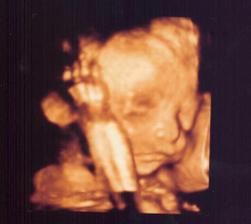

Naša bábika